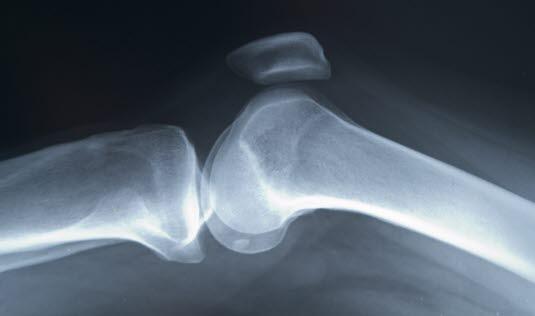

Lengdeveksten av rørknokler foregår i noe som kalles epifyseskiver. Disse er bruskskiver eller plater av brusk som befinner seg mellom epifysen og diafysen. Bruskcellene deler seg og gjør at knokkelen forlenges. Etter hvert dør bruskcellene nederst mot diafysen, og området fylles av vev bestående av mye osteoblaster. Disse står for dannelsen av nytt beinvev der det tidligere var brusk. Både bruskvevet og beinvevet vokser i starten med omtrent like stor hastighet, men etter en tid vokser beinvevet raskere enn bruskvevet og tar det til slutt igjen. Når beinvevet har vokst så mye at vi kun har en tynn stripe brusk igjen (epifyselinjen), har veksten stanset og videre lengdevekst er ikke mulig.